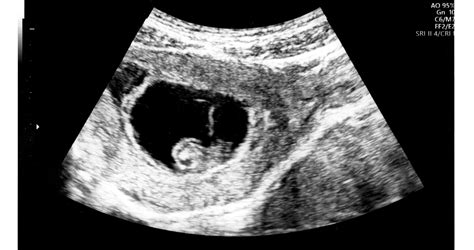

A méhen belüli magzati ártalmaknak sokszor nincs semmiféle olyan tünete, amelyet az anya érzékelne. Praenatalis diagnosztikának, azaz magzati korban történő vizsgálóeljárásnak hívják azokat a módszereket, amelyek a fejlődési rendellenességek felismerésére irányulnak. Szűrővizsgálatokkal - ultrahanggal, laborvizsgálatokkal, magzatvíz- és méhlepényszövet-mintavétellel - tárják fel a problémákat. Fontos, hogy az anyát is ki kell kérdezni, hogy volt-e valamilyen betegsége, be van-e oltva egyes vírusok (Rubeola vagy bárányhimlő) ellen. A 12. héten végeznek először genetikai ultrahangos szűrővizsgálatot.